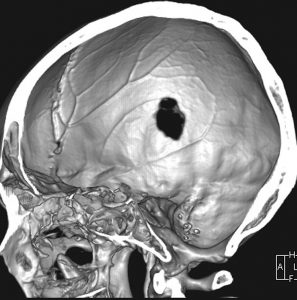

- 上の写真は,子供の右の頭頂骨にできたLCHで,頭部病変では最も多く見られるタイプです

- 頭蓋骨が丸く抜けるように破壊されるのでpunched out lesionと表現されます

9歳の男の子です。右側頭部が腫れてきたのに気づきました。頭蓋骨のいびつな破壊像があります。

この病変は単発(孤発)病変ですが,ややいびつな形をしていて,頭皮の方に盛り上がっていますから,活動性の病変です。手術で完全摘出すると治りますから,骨欠損が広がるようなら手術したほうがいいです。理由は,手術が簡単なこと,病理診断がつくこと,これ以上の病変の広がりを抑えることです。最近は自然の骨に近いような人工骨で補填することができますが,骨形成しなくても自然修復で骨形成されます。とくに,低年齢児では骨形成をしない時もあります,頭蓋骨が自然再生するからです。